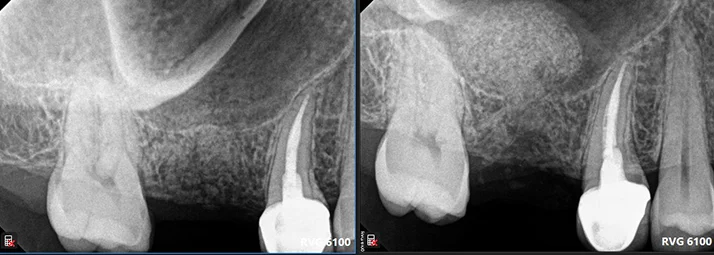

Soft Tissue Grafting

Soft tissue management is very important to ensure the longevity of dental implants. With only sufficient alveolar bone but insufficient healthy gum, implants would be jeopardized in periodontal bone loss, gingival recession, titanium implant surface metal showing, peri-implantitis and implant failure.

Proper soft tissue management can assure the life of dental implants. In this case, we used free gingival graft to increase the volume of the keratinized gum tissue around the implants.